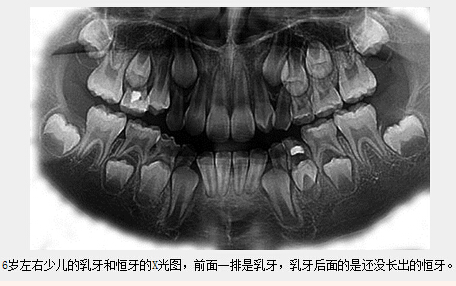

兒(er) 童乳牙列和恒牙列